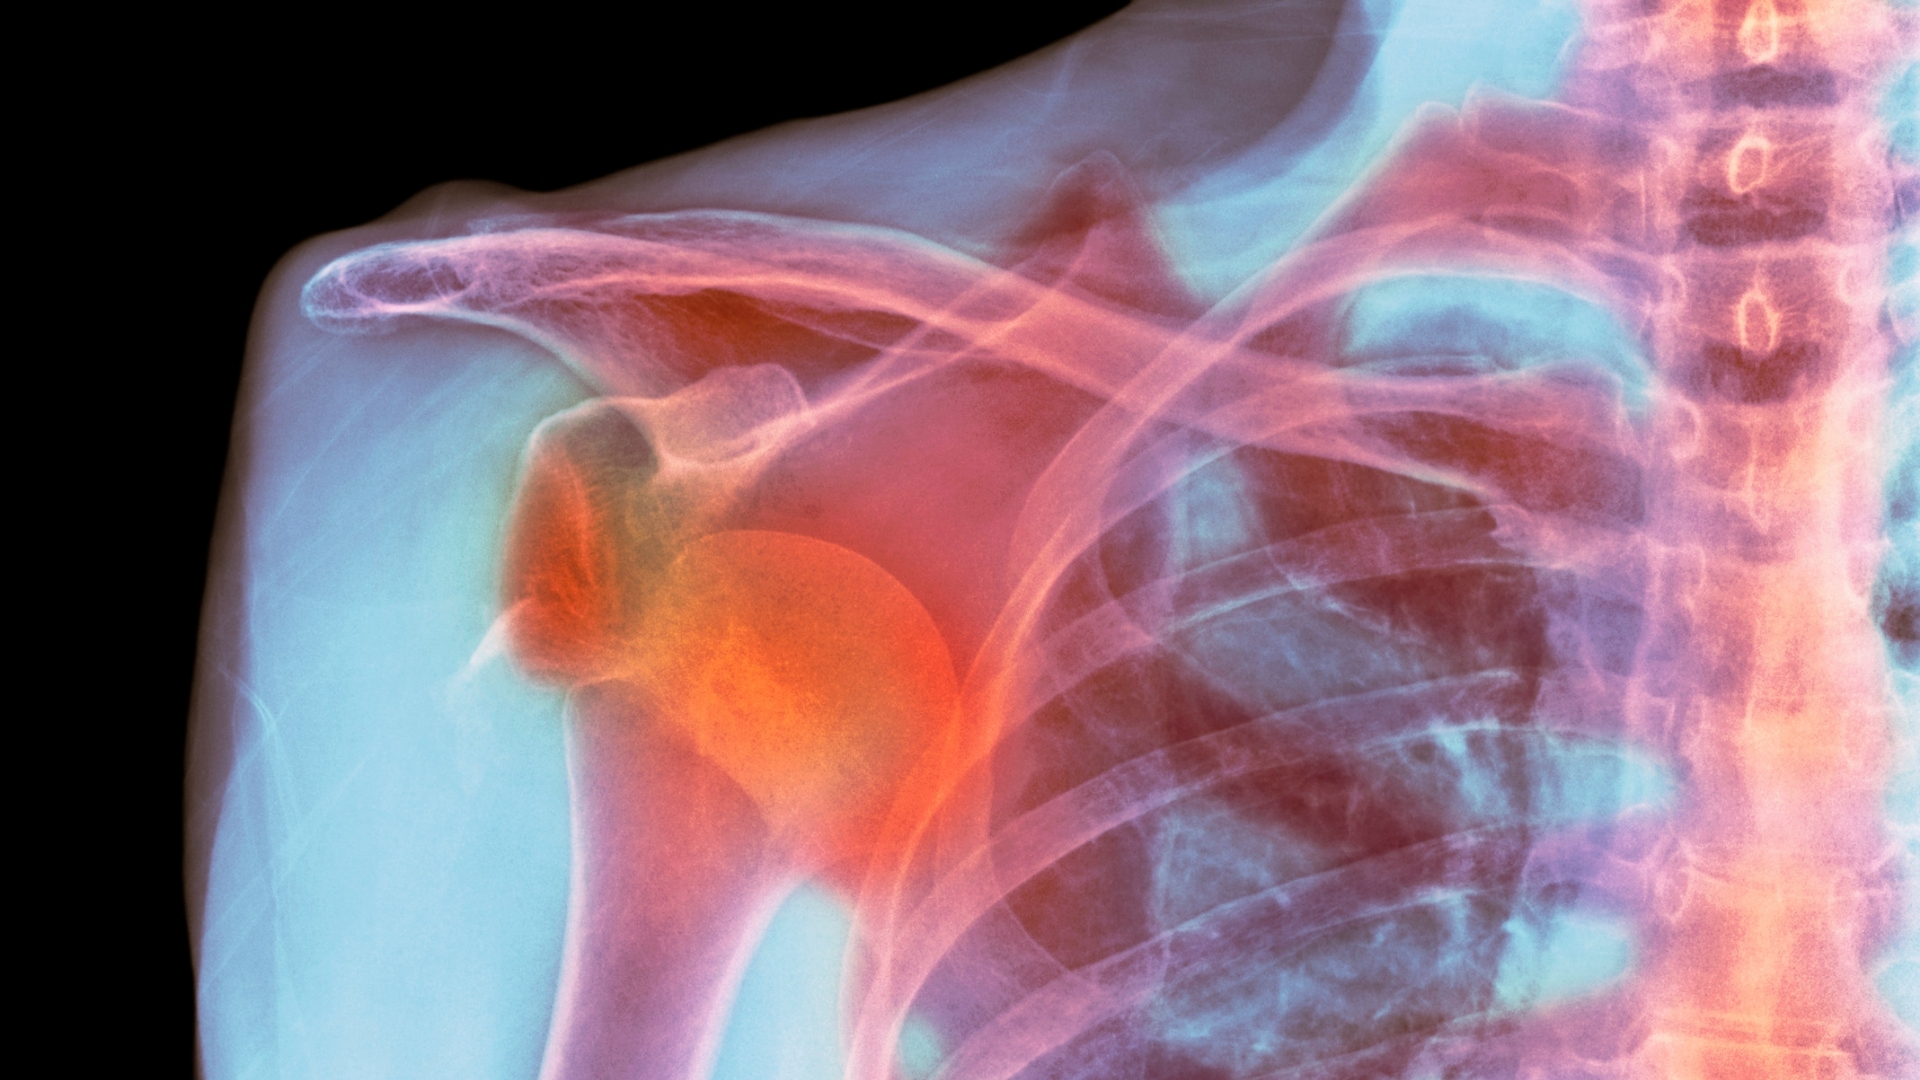

Trật khớp vai tái hồi là tình trạng khớp vai bị trật lặp đi lặp lại sau chấn thương ban đầu, thường gặp ở người trẻ và vận động viên. Nếu không can thiệp đúng cách, tình trạng này có thể gây suy giảm chức năng vai và ảnh hưởng lâu dài đến chất lượng cuộc sống.

Trật khớp vai tái hồi là tình trạng đầu xương cánh tay (chỏm xương cánh tay) liên tục trượt ra khỏi ổ chảo của xương vai do cấu trúc giữ khớp bị tổn thương sau lần trật khớp ban đầu. Đây là một trong những biến chứng phổ biến nhất sau trật khớp vai cấp tính, đặc biệt ở người trẻ, nam giới và những người thường xuyên tham gia các hoạt động thể thao hoặc lao động gắng sức.

Trong lần trật khớp đầu tiên, bao khớp, dây chằng và sụn viền quanh ổ chảo thường bị rách hoặc giãn. Sự tổn thương này khiến khớp vai trở nên lỏng lẻo và dễ bị trật lại, thậm chí chỉ với các động tác thông thường như giơ tay lên cao, xoay vai mạnh hoặc bị va chạm nhẹ. Mỗi lần trật khớp tiếp theo không những làm tăng nguy cơ tổn thương thêm các cấu trúc quanh khớp mà còn gây giảm chức năng vận động và đau kéo dài.